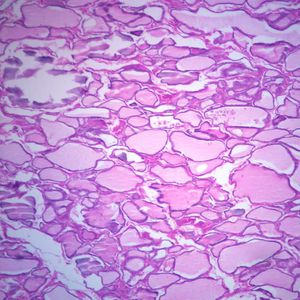

Human Thyroid, sec. 7 m H&E Microscope Slide

Product review & video